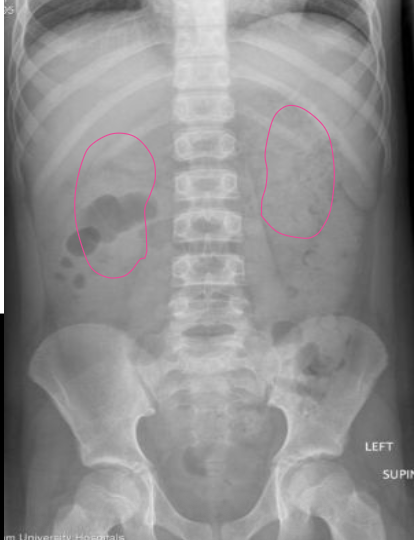

Kidneys

What anatomy is outlined in this image?